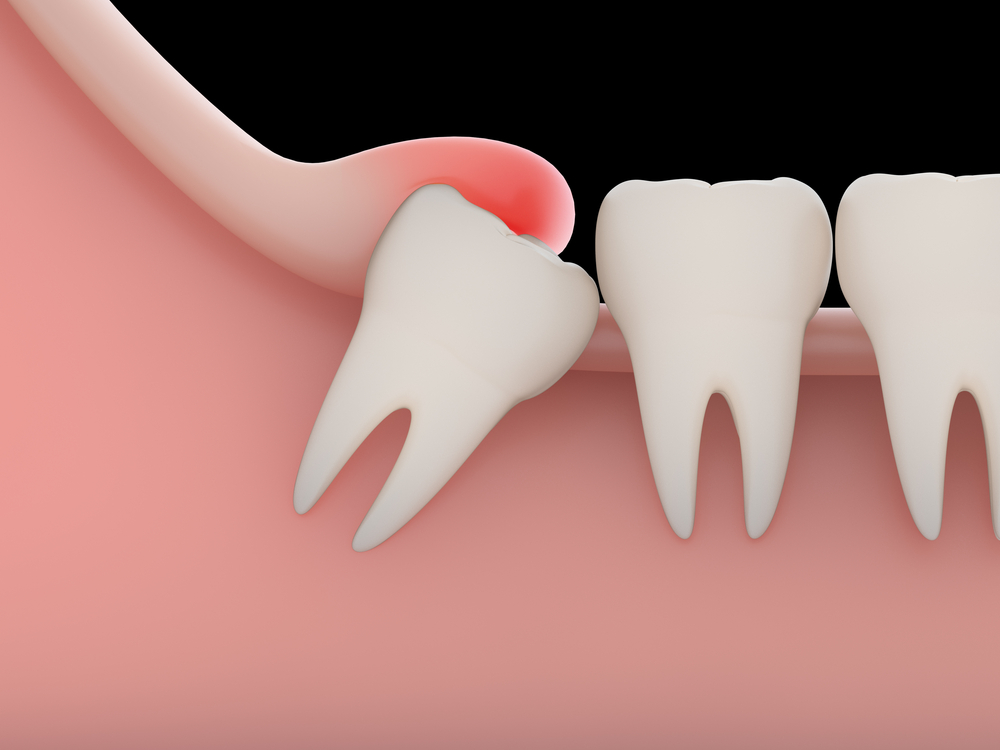

Oral surgery refers to surgical procedures performed in the mouth and jaw to address issues like impacted teeth, severe decay, jaw misalignment, infections, or preparation for implants. Common procedures include tooth extractions, wisdom tooth removal, bone grafting, and minor soft tissue surgeries. We prioritize careful diagnosis, minimally invasive methods, and thorough follow-up to support a smooth recovery.

• Have impacted or problematic wisdom teeth

• Need a tooth removed due to infection, trauma, or decay